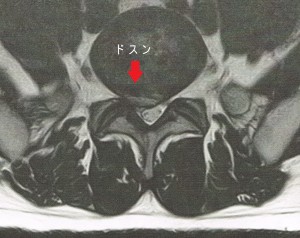

弁護士事務所から紹介を受け、被害者から症状を聞き取ると「太ももからアキレス腱までのしびれがひどい」とのこと。早速、MRI画像を見るとL5-S1間に正中から右神経根にかけてドスンとした椎間板ヘルニアがある。久々に12級狙いの案件である。

12級であるべきを不可解な14級判断。異議申立を準備するも、初回が万全である故、新たな医証などない。ほぼそのままの書類に加え、再度MRIを撮影し、主治医に継続して治療している旨の診断書を記載いただく。異議申立の建前に乗っ取り、医証を追加する不毛な作業となった。

そして2か月後、12級の変更回答。最初から出せばいいのに何をもったいぶっているのか・・・それだけ12級判断は慎重であるのはわかるが、やはり担当者のおざなりな審査(初回審査では画像所見をしっかり検討していないのではないか?)を感じざるをえない事案であった。